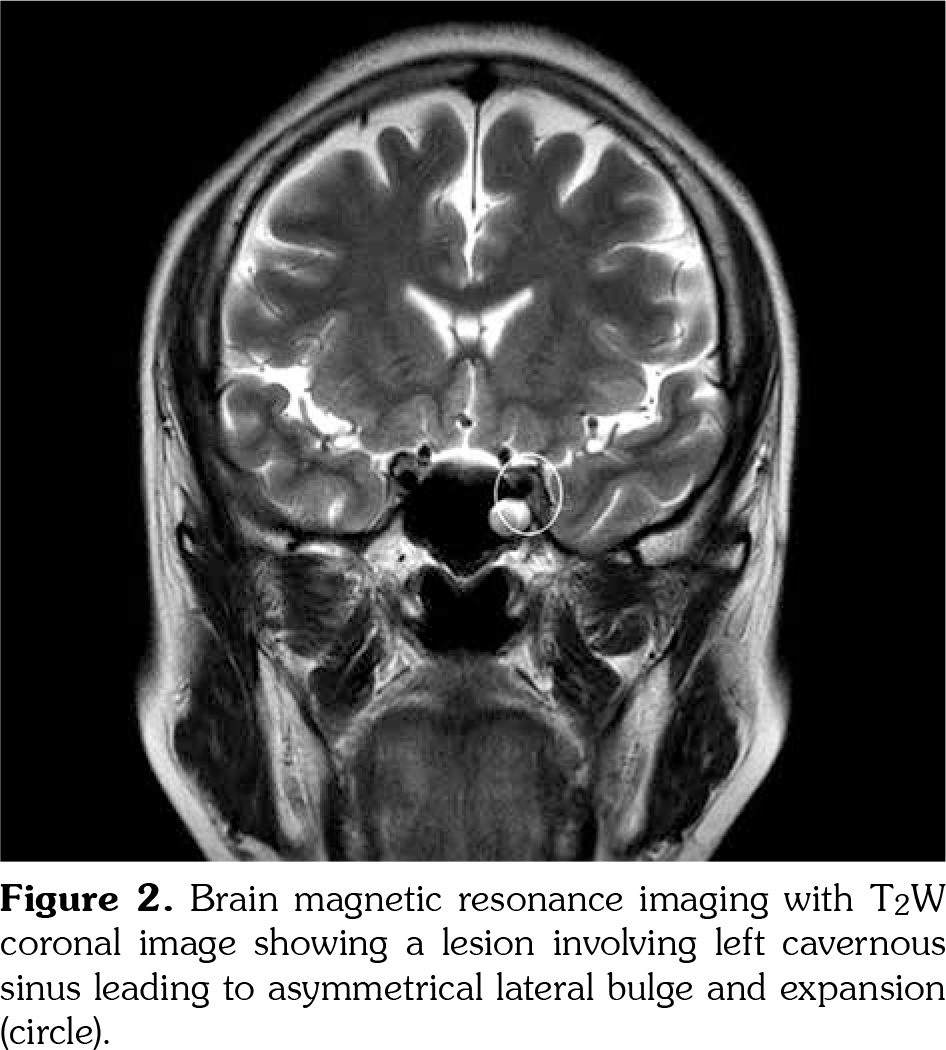

A 53-year-old female patient visited our clinic with complaints of sudden onset of orbital pain, ipsilateral headache and intermittent diplopia. The severe, lancinating pain was aggravated with eyeball movements. Previously, she had been diagnosed with BD based on recurrent oral and genital ulcers and a positive pathergy test. She tested positive for human leucocyte antigen B51. She remained on colchicine 1.2 mg/day and had been asymptomatic for 12 years. She denied a history of hypertension, diabetes, malignancy, asthma or hyperthyroidism. The pupils reacted normally to light and were of equal size. Visual acuity was 20/20 in each eye. Mild hypertropia was observed on the left. Limited inferior rectus movement was found among the nine cardinal extraocular movements associated with diplopia (Figure 1). Neither papilledema nor raised intraocular pressure was found. The remaining neurological examination was normal. Laboratory parameters including complete blood count, muscle enzymes, sedimentation rate, C-reactive protein, antinuclear antibodies, double-stranded deoxyribonucleic acid antibodies, anti-neutrophil cytoplasmic antibodies, C3, C4 antiphospholipid, anticardiolipin, and β2 glycoprotein antibodies, proteins C and S, and thyroid function were all within normal range. Magnetic resonance imaging (MRI) of the brain demonstrated bulging and expansion of the left cavernous sinus (Figure 2) due to thrombosis. Cerebrospinal fluid examination was unrevealing. Finally, she was diagnosed with Tolosa-Hunt-like syndrome associated with BD. The patient was started on a course of intravenous methylprednisolone (1 g/day for five days). On day three of the treatment, she had a considerable relief of retro-orbital pain and headache. Two weeks later, noticeable improvement in ophthalmoplegia was observed following treatment with oral prednisolone 50 mg/day. After eight weeks, she showed complete resolution of diplopia. Six months later, the patient remained on oral prednisolone 7.5 mg/day without recurrence.